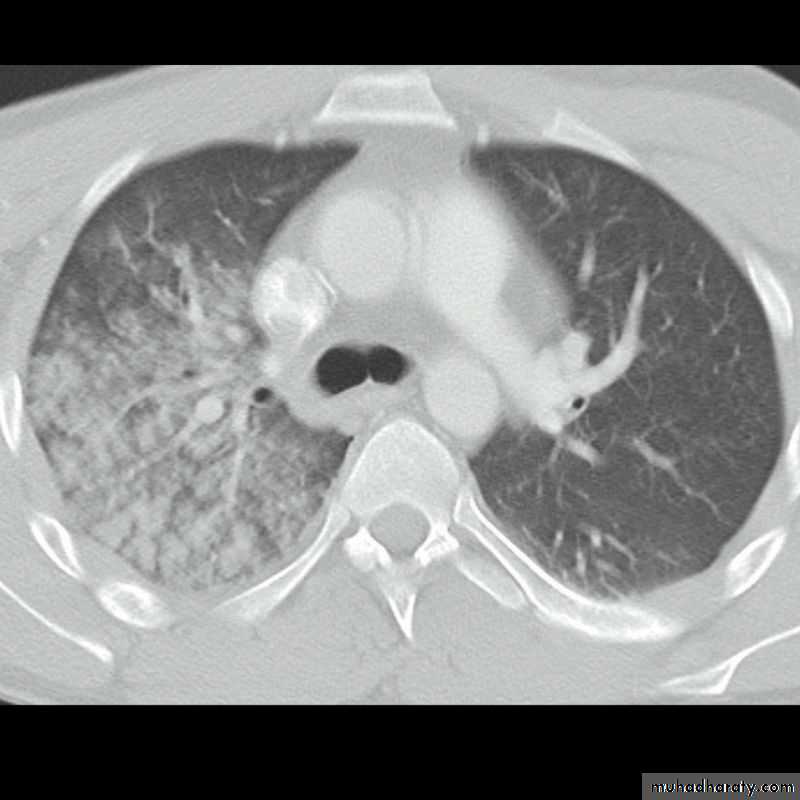

Area of hypertranslucensy (pneumothorax)

What is the difference?

(emphysematous bullae) (pneumothorax)